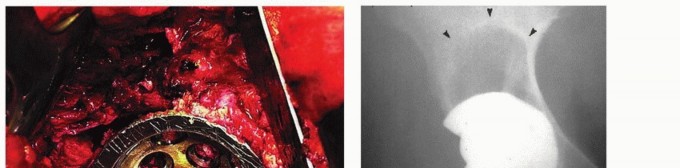

هشاشة العظام حول مفصل الورك الاصطناعي هي تآكل عظمي شائع بعد جراحة استبدال مفصل الورك الكلي، غالبًا بسبب جزيئات البولي إيثيلين. يبدأ العلاج بالتشخيص الدقيق عبر الأشعة المقطعية، ويُعد تبديل بطانة البولي إيثيلين حلاً فعالاً للمكونات الثابتة، مما يقلل الألم ويستعيد وظيفة المفصل بفضل خبرة الأستاذ الدكتور محمد هطيف.

الخلاصة الطبية السريعة: هشاشة العظام حول مفصل الورك الاصطناعي هي تآكل عظمي شائع بعد جراحة استبدال مفصل الورك الكلي، غالبًا بسبب جزيئات البولي إيثيلين. يبدأ العلاج بالتشخيص الدقيق عبر الأشعة المقطعية، ويُعد تبديل بطانة البولي إيثيلين حلاً فعالاً للمكونات الثابتة، مما يقلل الألم ويستعيد وظيفة المفصل بفضل خبرة الأستاذ الدكتور محمد هطيف.

يتناول هذا المقال الأسباب والتشخيص وخيارات العلاج لهشاشة العظام التي تحدث حول مكونات الحُق الثابتة ![توضيح طبي: هشاشة العظام حول مفصل الورك الاصطناعي تبديل بطانة البولي إيثيلين الحل الأمثل](/media/upload/ad023e43-fc70-4c74-a667-a1eb6d8e107d.jpg) ![توضيح طبي: هشاشة العظام حول مفصل الورك الاصطناعي تبديل بطانة البولي إيثيلين الحل الأمثل](/media/upload/e718bae5-3e04-4049-b408-451d4ebed9ed.jpg) ![توضيح طبي: هشاشة العظام حول مفصل الورك الاصطناعي تبديل بطانة البولي إيثيلين الحل الأمثل](/media/upload/436dcac0-c732-444a-8403-539f5c46ae88.jpg) ![توضيح طبي: هشاشة العظام حول مفصل الورك الاصطناعي تبديل بطانة البولي إيثيلين الحل الأمثل](/media/upload/5295a9df-4504-4c8c-89b3-71233cb41476.jpg) ![توضيح طبي: هشاشة العظام حول مفصل الورك الاصطناعي تبديل بطانة البولي إيثيلين الحل الأمثل](/media/upload/c2411af8-be23-4562-90d6-94b6e9d0c0d9.jpg) ![توضيح طبي: هشاشة العظام حول مفصل الورك الاصطناعي تبديل بطانة البولي إيثيلين الحل الأمثل](/media/upload/eda756a8-6677-4b09-b6f5-3619857552e2.jpg) ![توضيح طبي: هشاشة العظام حول مفصل الورك الاصطناعي تبديل بطانة البولي إيثيلين الحل الأمثل](/media/upload/d199b219-f355-4caf-85c3-a764f4913cb3.jpg) ![توضيح طبي: هشاشة العظام حول مفصل الورك الاصطناعي تبديل بطانة البولي إيثيلين الحل الأمثل](/media/upload/ddd6b344-5b51-450e-8239-8e832b923988.jpg) ![توضيح طبي: هشاشة العظام حول مفصل الورك الاصطناعي تبديل بطانة البولي إيثيلين الحل الأمثل](/media/upload/86786efa-0a81-438c-984d-749c462862d5.jpg) ---